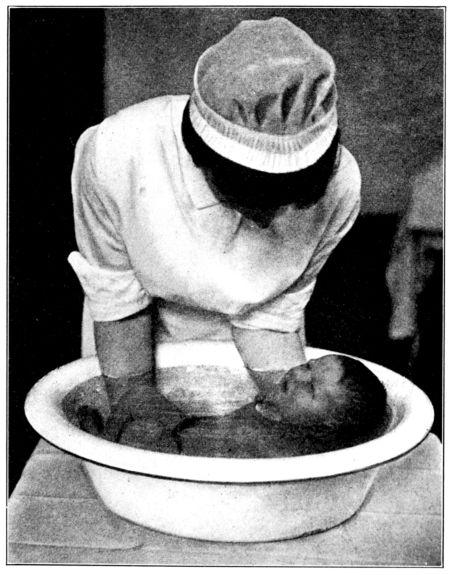

| 154. | Bathing the baby | 467 |